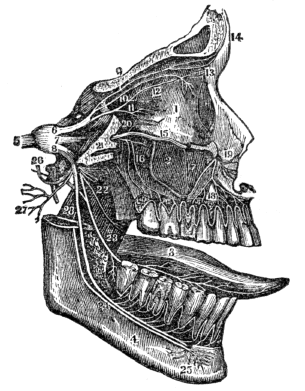

| 42. | Anatomy of the Organs of Taste, | 384 |

| 42. | Physiology of the Organs of Taste, | 386 |

| 43. | Anatomy of the Organs of Smell, | 389 |

| 43. | Physiology of the Organs of Smell, | 391 |